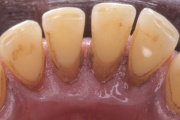

- igemepiir on taandunud (3)

- hamba kinnitussidemete kadu (3)

- hammaste tundlikkus (9)